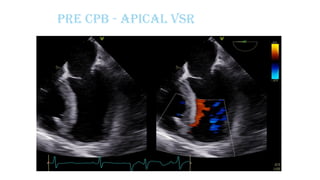

Pre CPB - Apical VSR

Pre CPB – Apical VSR showing multiple jets

across thin apical septum

oApical VSR+,

oIt is a complex VSR at the apical ventricular septal level showing

multiple jets across the thin apical septum.

oQp/Qs=2.0